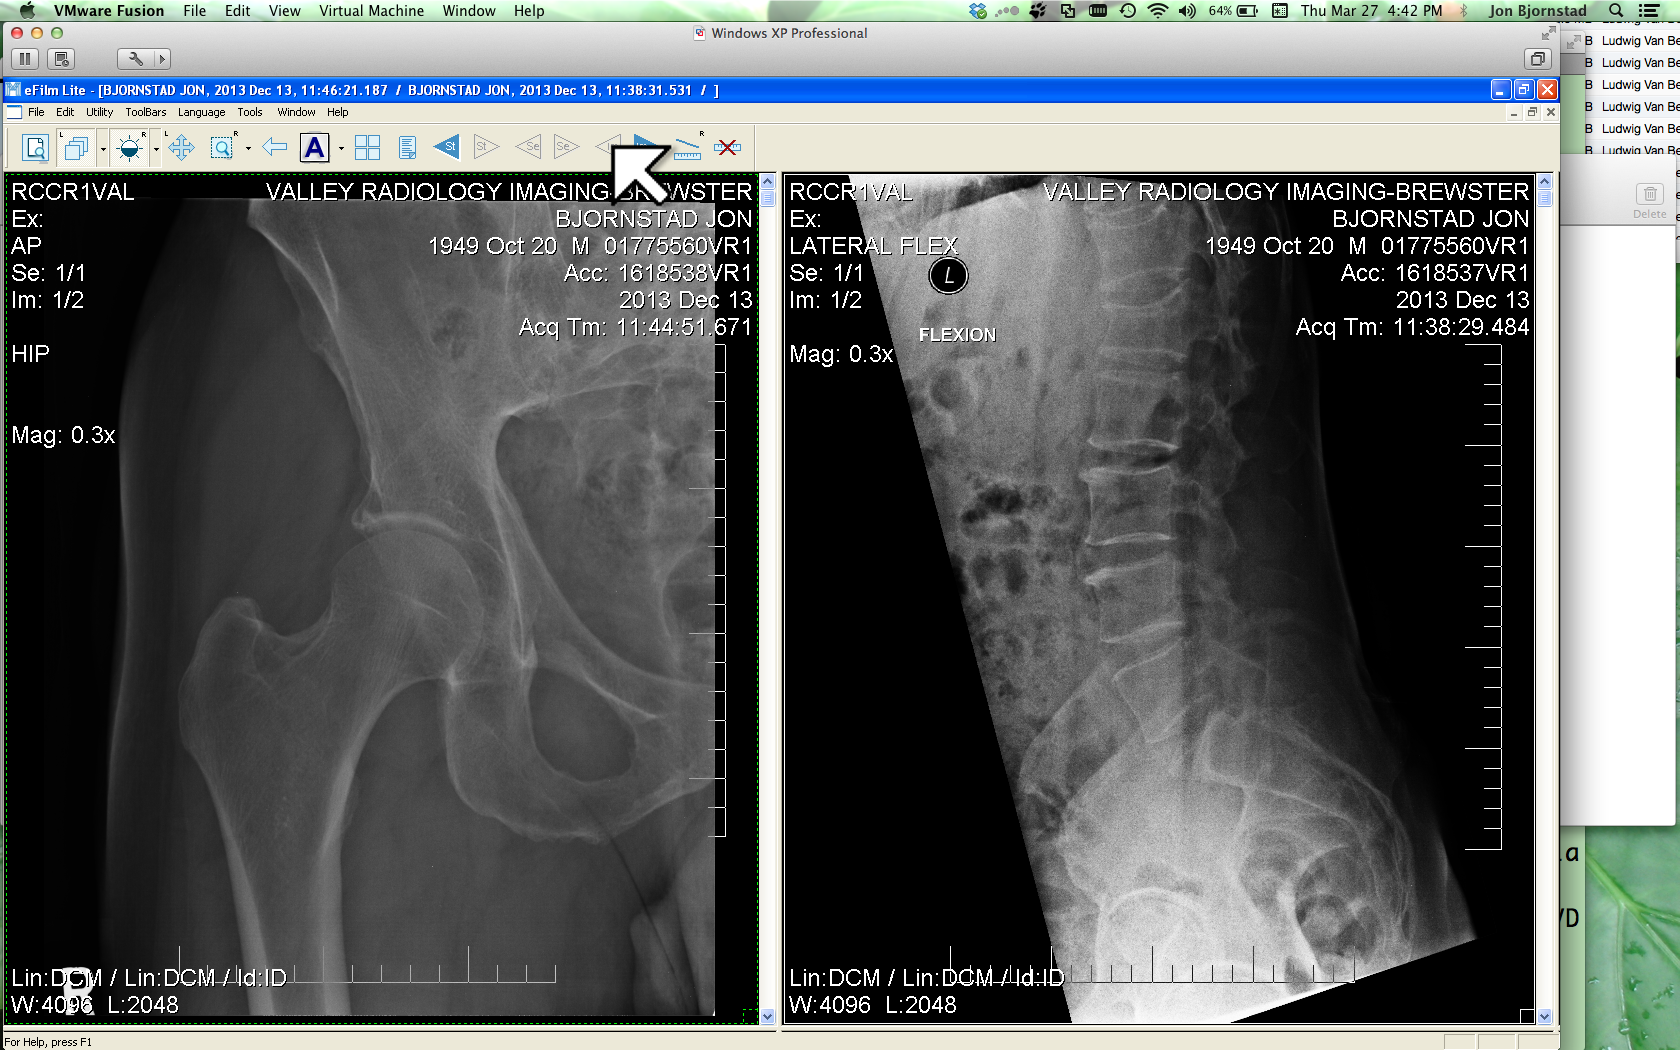

I was called and brought to a room. The male nurse said that I should put on a gown in preparation for having an X-ray taken and he gave me a warm blanket. Somehow I got out of my clothes and socks and shoes. I didn't want to try and get up on the gurney/bed thing. Just remained in the chair.

Doctor came in. He palpated my hips, spine, legs, arms, shoulders. I asked what he was doing. He said he was listening to see if and when I would yell "Ouch". His fairly quick expert assessment was that nothing was broken and that no X-Ray was needed. He prescribed ice packs for the next 2-3 days and then heat. And that he would give me a prescription for pain medications. Ibuprofen and Oxycodone, as needed. He said that I was lucky. It could have been much worse. I asked if a planned 3 hour trip to Fresno would be possible. He said yes but that for my comfort it would be best to periodically stop to walk about and change position and rest.